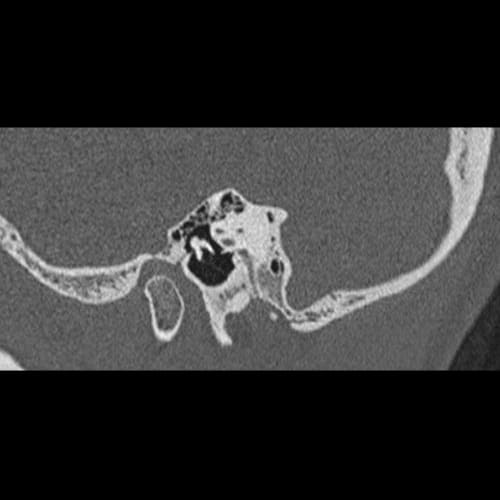

Sagittal